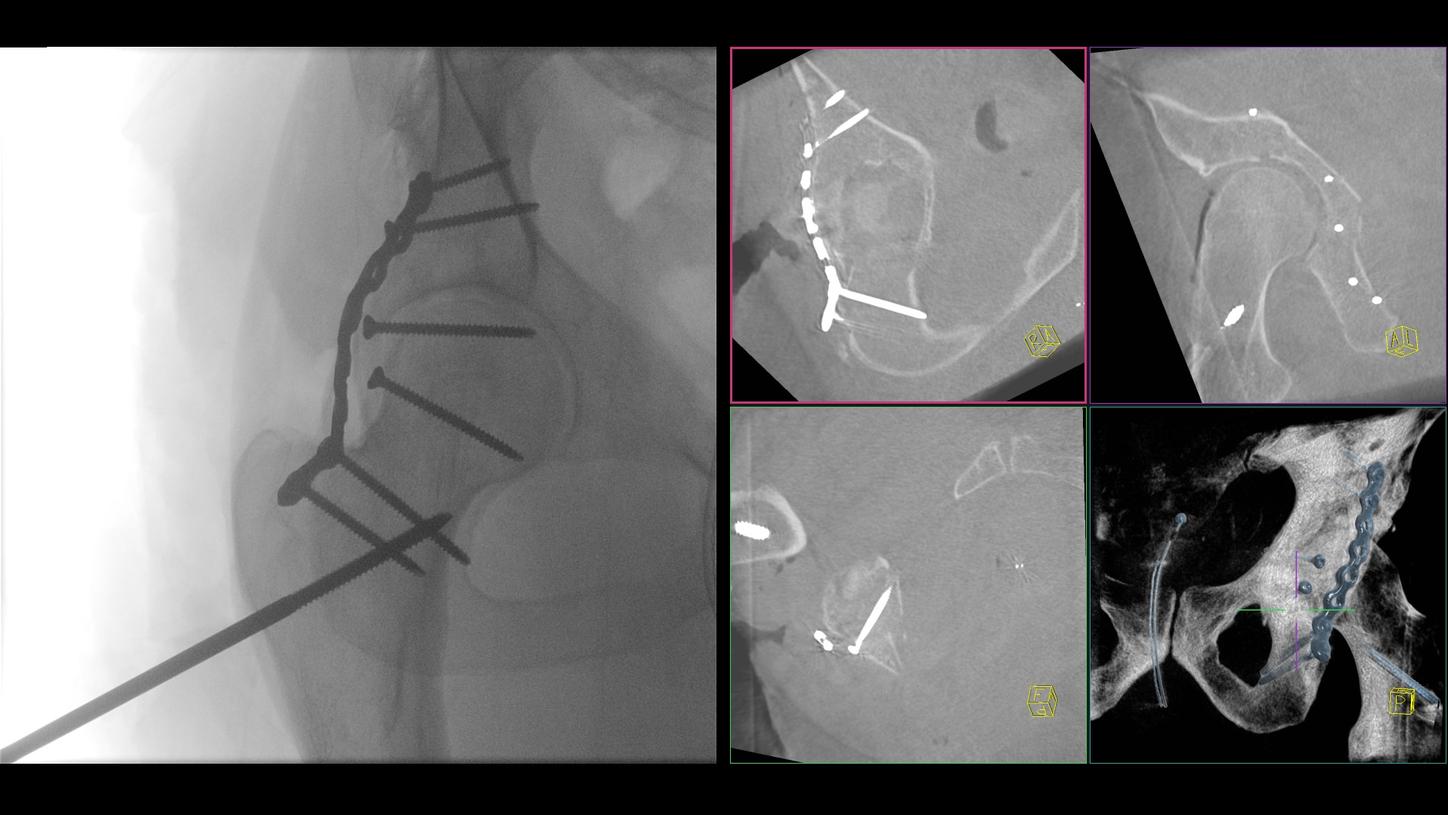

A preclinical study confirmed intraoperative-imaging time savings of up to 55% in pelvic surgery, enabled by the self-driving and automation technologies of CIARTIC Move.

CIARTIC Move already has proven its benefits  in a preclinical study1: The system enabled significant time savings for all three anatomical regions included in the study (pelvis, spine, distal radius).

Benefit from precise 2D and 3D visualization of anatomical structures and metallic objects with excellent image quality.

A preclinical study confirmed intraoperative-imaging time savings of up to 55% in pelvic surgery, and proved that a single person could operate the system independently from inside the sterile field.